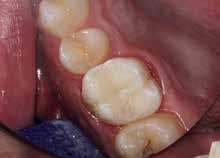

Bei der Diagnose des schmerzfreien Patienten stellte sich die beschriebene Erhebung schließlich als Fistel heraus (Abb. 1). Der Zahn 26 sowie die Nachbarzähne wurden zunächst einer Sensibilitätsprüfung unterzogen, wobei der Kältetest an Zahn 26 negativ ausfiel. Im Anschluss erfolgte dann die Anfertigung der diagnostischen Röntgenaufnahmen (Abb. 2 und 3). Dazu wurde ein Guttapercha-Stift in den Fistelgang eingebracht, um die Lokalisation der Entzündung zu erleichtern. Speziell bei der distal exzentrischen Aufnahme ließ sich dabei an 2 Wurzelspitzen des Zahns 26 die Entzündung ausmachen (Abb. 2). Insofern war in diesem Fall eine endodontische Behandlung des Zahnes angezeigt. Für diese wurde sogleich ein Folgetermin vereinbart.